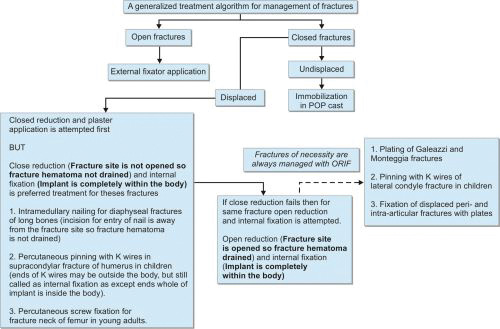

A treatment algorithm for management of fracture is given in Flowchart 1.1.